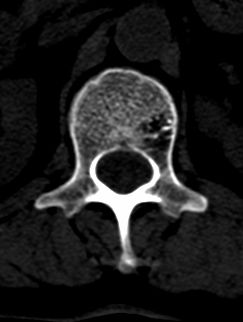

患者 女 54岁 外伤后检查发现l1椎体局部密度减低,请问这是什么病灶?

椎体内部局限性骨小梁稀疏、粗大改变,周围未见软组织肿块,首先考虑椎体血管瘤。